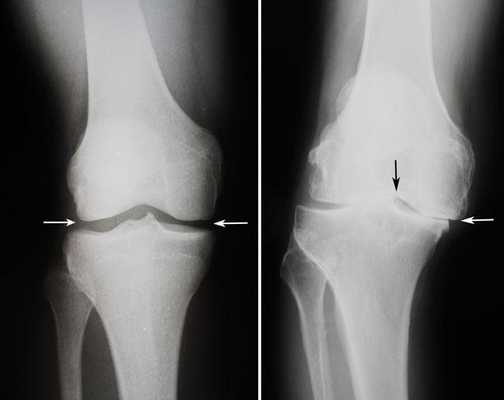

Артроз коленного сустава на рентгене.

Показания к замене

Посмотрите на рентген, на нем вы видите, до какой степени при запущенном гонартрозе изношен гиалиновый хрящ, обеспечивающий гладкое скольжение суставных поверхностей. Концевые участки костей грубо деформируются нарушая функции сгибания и разгибания конечности вызывая интенсивный болевой синдром.

Динамика болезни на рентгене.